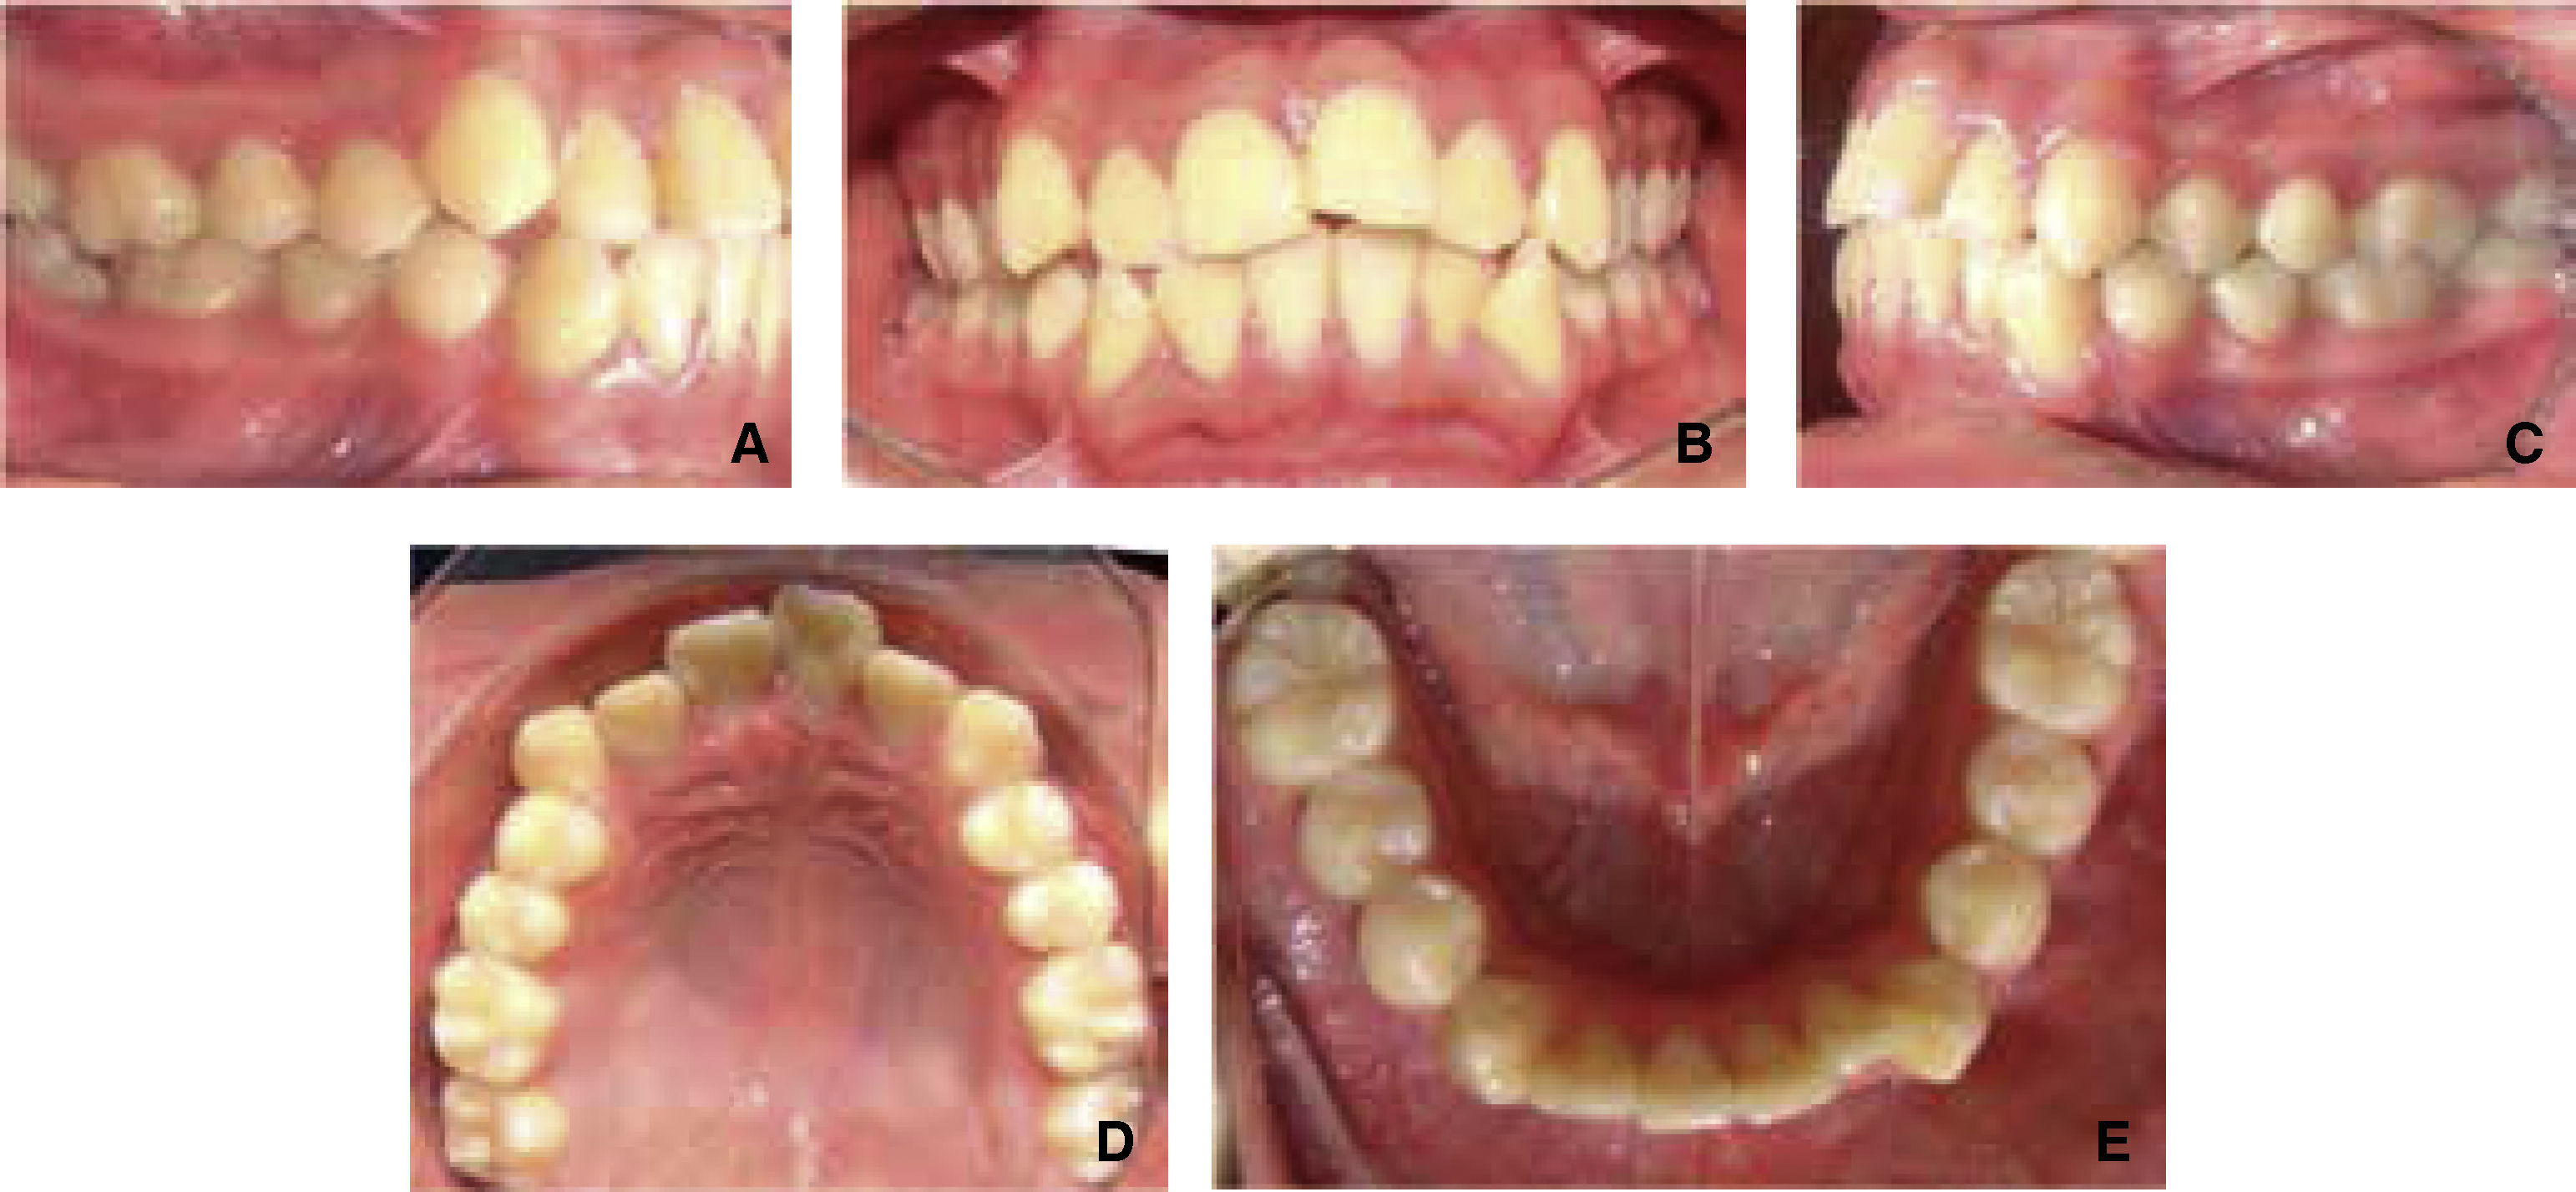

An increased lower facial third is observed in the facial analysis, as well as a convex proifle, hypertonic perioral muscles and a facial midline that coincides with the upper dental midline (Figure 1).

Lower dental midline deviated to the left was observed in the intraoral analysis, as well as severe upper and lower anterior crowding, proclined upper left central incisor, upper right lateral incisor edge to edge with the lower canine, overjet 6mm and overbite 1mm (Figure 2). Mesial inclination and infraocclusion of the lower second molar was also observed. Right side and left side molar and canine Class I as well as palatal inclination of the upper left lateral incisor was observed.